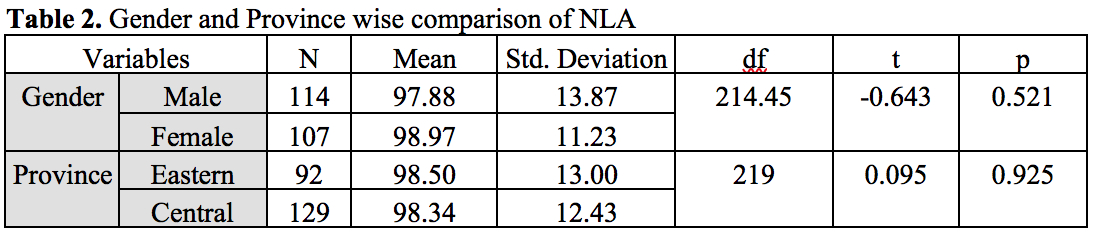

Methods: 221 lateral cephalometric radiographs of patients aged between 16–26 years (male [n=114] and female [n=107]) belonging to central and eastern regions of Saudi Arabia was taken from Orthodontic clinics database among Riyadh and eastern regions, Saudi Arabia. OnyxCeph3TM (Image Instruments GmbH Olbernhauer Str. 5 D 09125 Chemnitz Germany) digital software was used to analyze the dentoskeletal classification of the sample as Class I (n=84), Class II Division 1 (n=42), Class II Division 2 (n=33), Class III (n=62). Burstone analysis of six linear measurements for facial soft tissue thickness (FSTT) was used. All statistical analyses were set at a significant level of when (P<0.05).

Methods: 221 lateral cephalometric radiographs of patients aged between 16–26 years (male [n=114] and female [n=107]) belonging to central and eastern regions of Saudi Arabia was taken from Orthodontic clinics database among Riyadh and eastern regions, Saudi Arabia. OnyxCeph3TM (Image Instruments GmbH Olbernhauer Str. 5 D 09125 Chemnitz Germany) digital software was used to analyze the dentoskeletal classification of the sample as Class I (n=84), Class II Division 1 (n=42), Class II Division 2 (n=33), Class III (n=62). Burstone analysis of six linear measurements for facial soft tissue thickness (FSTT) was used. All statistical analyses were set at a significant level of when (P<0.05).